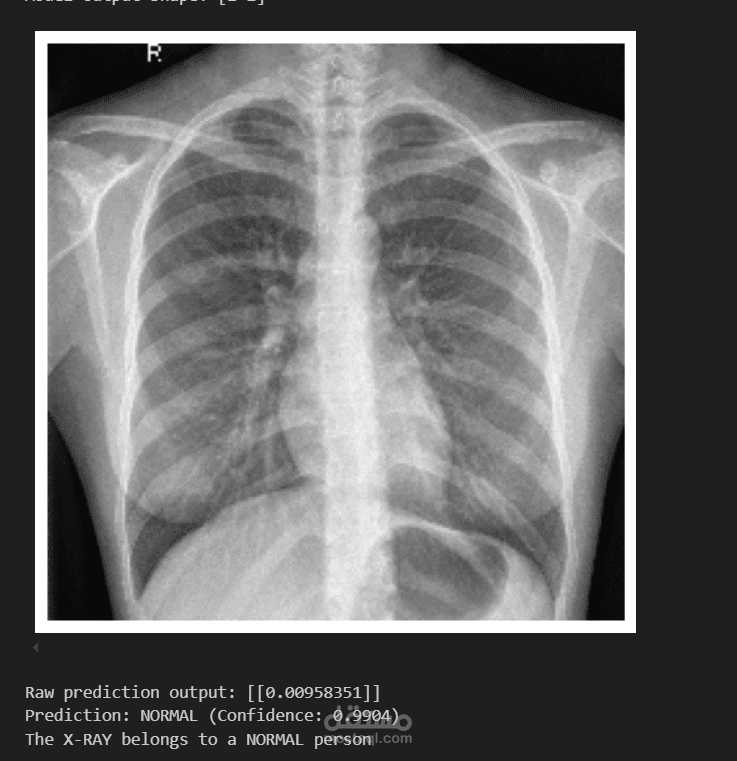

يهدف هذا المشروع إلى تطوير نموذج دقيق لاكتشاف الالتهاب الرئوي من صور الأشعة السينية (X-ray) باستخدام تقنيات التعلم العميق. تم استخدام نموذج EfficientNetB0 كنموذج أساسي، حيث أظهر أداءً ممتازًا وحقق دقة بلغت 99% على مجموعة البيانات المستخدمة. كما تم أيضًا استخدام نموذج VGG19 كجزء من عملية المقارنة والتجريب بهدف تعزيز الأداء وتحليل النتائج.

تقييم أداء النماذج باستخدام مؤشرات مثل الدقة (Accuracy)، الحساسية (Recall)، والتخصص (Specificity).

عرض نتائج التنبؤ بصريًا من خلال مصفوفة الالتباس (Confusion Matrix) ومخططات أخرى.

هذا المشروع يُظهر فعالية النماذج الحديثة مثل EfficientNetB0 و VGG19 في الكشف المبكر عن الالتهاب الرئوي، مما يعزز من فرص التشخيص السريع والدقيق في المجال الطبي.